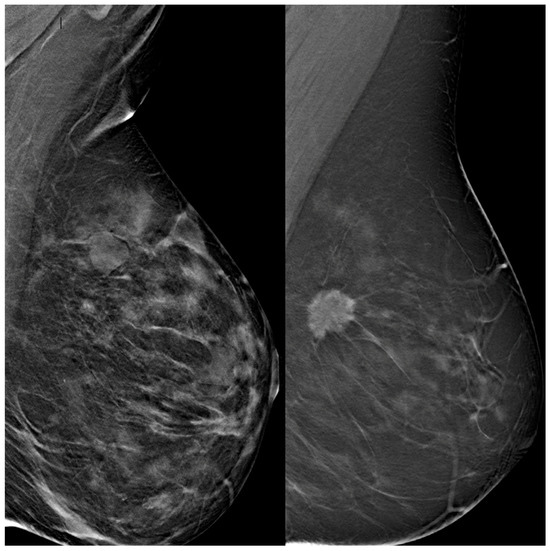

2.4. Radiomic Workflow and Software

Deep learning analysis was performed using the Trace4Research™ radiomic platform (DeepTrace Technologies S.R.L., v2.0–01, https://www.deeptracetech.com/files/Trace4Research_TechnicalSheet_v2-0-01.pdf, accessed on 3 September 2024). This platform supports (i) VOI segmentation from DBT images, (ii) preprocessing of input volumes, (iii) data augmentation, and (iv) supervised training, validation, and testing of convolutional neural network (CNN) architectures.

Segmentation of VOIs was manually performed slice by slice using the integrated segmentation tool. Two radiologists conducted the annotation: a board-certified radiologist with 3 years of experience and over 100 breast studies interpreted per year, and a radiology resident with 1 year of experience and fewer than 100 cases read annually.

Images were preprocessed through intensity discretization (256 bins) and resampled to a fixed dimension of 224 × 224 × 53 voxels, with the slice count representing the mean number across the dataset (Figure 1 and Figure 2).

Figure 1. TRACE4© platform: segmentation panel.